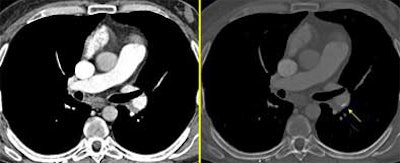

Calcification: Calcification of emboli is commonly seen in chronic PE. However, it can occur in a number of disorders, she said.

![]() |

| Calcification of embolic material. Maximum intensity projections (MIPS, above right, W: 1900 HU, C: 370 HU) are often helpful in distinguishing hard-to-find calcifications. |